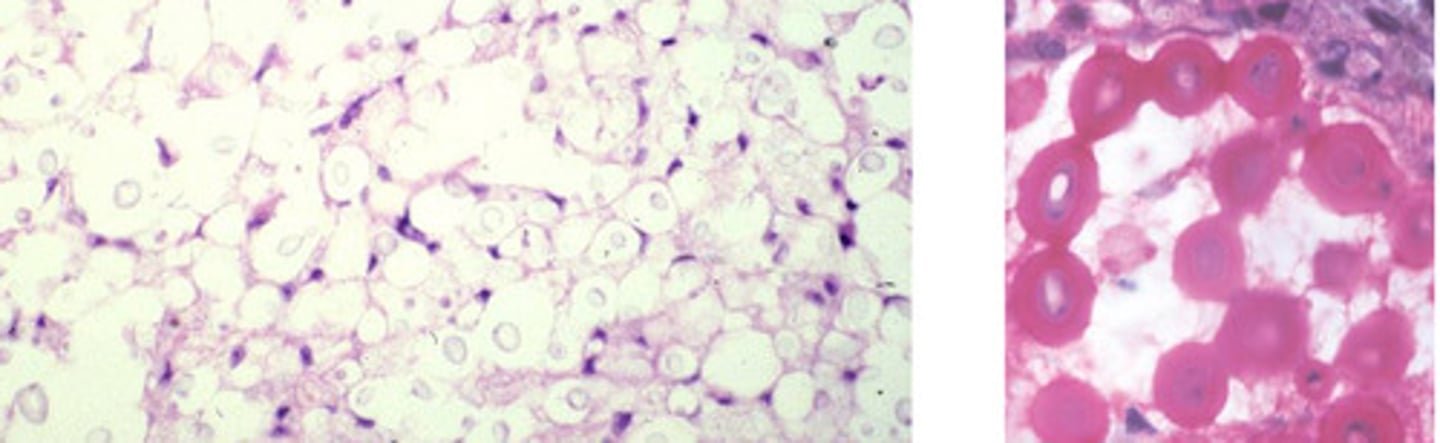

Aspergillus fumigatus

Identify the organism?